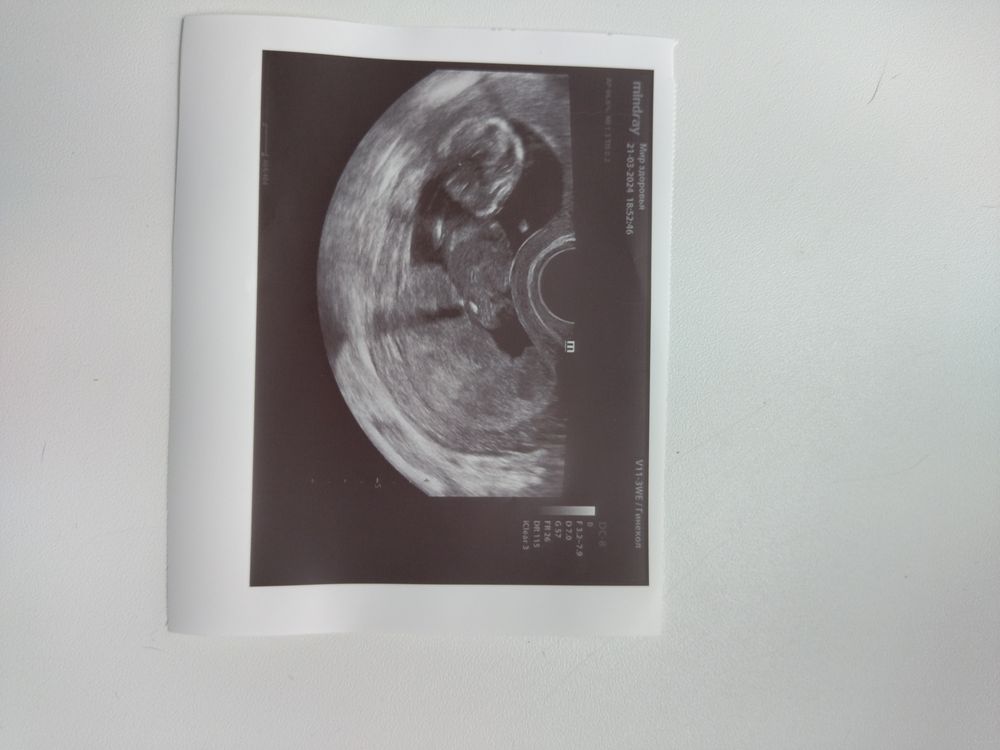

Изображение У меня девчуля выглядит так,но смотря последнюю фотку в коментах,думаю у вас девочка )

Да похожа на девчулю))) У меня сказали пацан, вот 12 недель)) Изображение

Просто Катя, там на УЗИ не совсем удобно лежит кроха, не вижу четко бугорок. А вот у вас прям парень, вообще не скрывает кто он😁

Ольга, ну вот тут да, похоже что девчонка и есть)

Ольга, я вижу девочку) ❤️ доча такая же была)